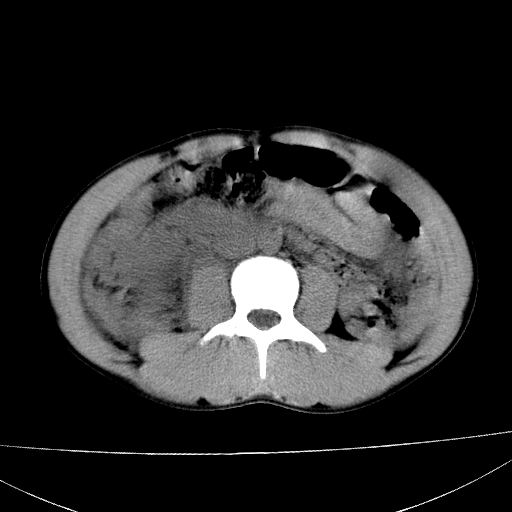

标题: CT15860:男,21岁,腹部外伤2小时伴胸疼。 [打印本页]

标题: CT15860:男,21岁,腹部外伤2小时伴胸疼。

b超示:肝破裂。

肝脏及肾脏明显有损伤性改变并激发腹腔内积液(血),以肝脏撕裂及肾周积血显著。

1)肝破裂伴腹腔积液(血)。2)右肾破裂伴右肾包膜下及肾周血肿。3)腹部空腔脏器穿孔可能。4)右侧少量胸腔积液(血)。

1)肝破裂伴腹腔积液(血)。2)右肾破裂伴右肾包膜下及肾周血肿。3)右侧少量胸腔积液(血)。

肝、右肾包膜下血肿,右侧腰大肌及腹膜后血肿;腹腔少量积血;腹腔疑有少量游离气体伴肠破裂。

1肝挫伤伴腹腔积液。2右肾挫裂伤伴右肾包膜及肾后间隙肿血肿。3右肾脏周围的积气,十二指肠显示结构不清,考虑十二指肠降部破裂可能性大。